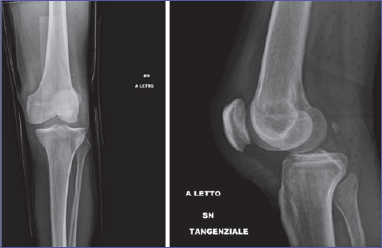

On inspection, the knee was swollen, an anatomical deformity with 90° knee flexion was noted. The patient did not complain of paresthesia or sensory deficits. The limb was warm and with palpable pulses. X-ray exam showed a PL knee dislocation (Fig. 1). Closed reduction and immobilization with posterior brace were performed, under conscious sedation, in the emergency department. Neurovascular status was closely monitored. Angio-CT scan was performed to exclude vascular injuries (Fig. 2). The patient was hospitalized. Neurovascular status, skin condition and clinical parameters were strictly monitored. The knee was unstable with persistent PL subluxation, worsened by dyskinesias, and both varus and valgus instability. The lesion was classified as a grade IV KD of Knee Dislocation Classification System. A staged multi-ligament reconstruction in two steps was planned: acute reparation of MCL and LCL and a staged reconstruction of both ACL and PCL. A neurologist was consulted to optimize the patient’s therapy with the aim of reducing the risk of recurrence. After 3 days we performed an acute surgical reparation of both the MCL and LCL. A 30° locked knee brace was placed. Postoperative X-rays exam (Fig. 3) showed perfect knee reduction. On the fifth postoperative day the patient was discharged with home care and an outpatient controls program. We planned to unlock the brace after 25 days, check the ligament status and then perform a knee MRI in order to plan an ACL-LCL reconstruction within 2 months. After 25 days, patient came to the outpatient department to unlock the brace. We noticed a relapse of PL subluxation with varus-valgus instability and failure of the MC and LCL reparation. The main causes of failure were the persistent and violent dyskinesias, due to Parkinson disease. In this context, plan a staged reconstruction would have been at high risk of another ligament failure. Thus, we talked with patient, and changed the strategy. Three months after the injury the patient was hospitalized and underwent, in general anesthesia, a total knee replacement with a hinged prosthesis (Fig. 4). We choose a hinged prosthesis to make the implant as stable as possible to resist dyskinesias. Postoperative anemia was observed, requiring the transfusion of 2 concentrated red blood cell units. No other postoperative complication was observed. From the day after surgery the patient started active and passive mobilization of the knee and a re-education protocol with full weight bearing. The patient was discharged on the 7th postoperative day to continue rehabilitation. Clinical and radiographic controls were performed at 3, 6, 12 months and then annual follow-up. At the last follow-up (3 years) the patient was walking without crutches, with full ROM, no pain and the same level of activity as before the injury (Fig. 5).

Figure 5.Clinical outcome at 3 years follow-up.